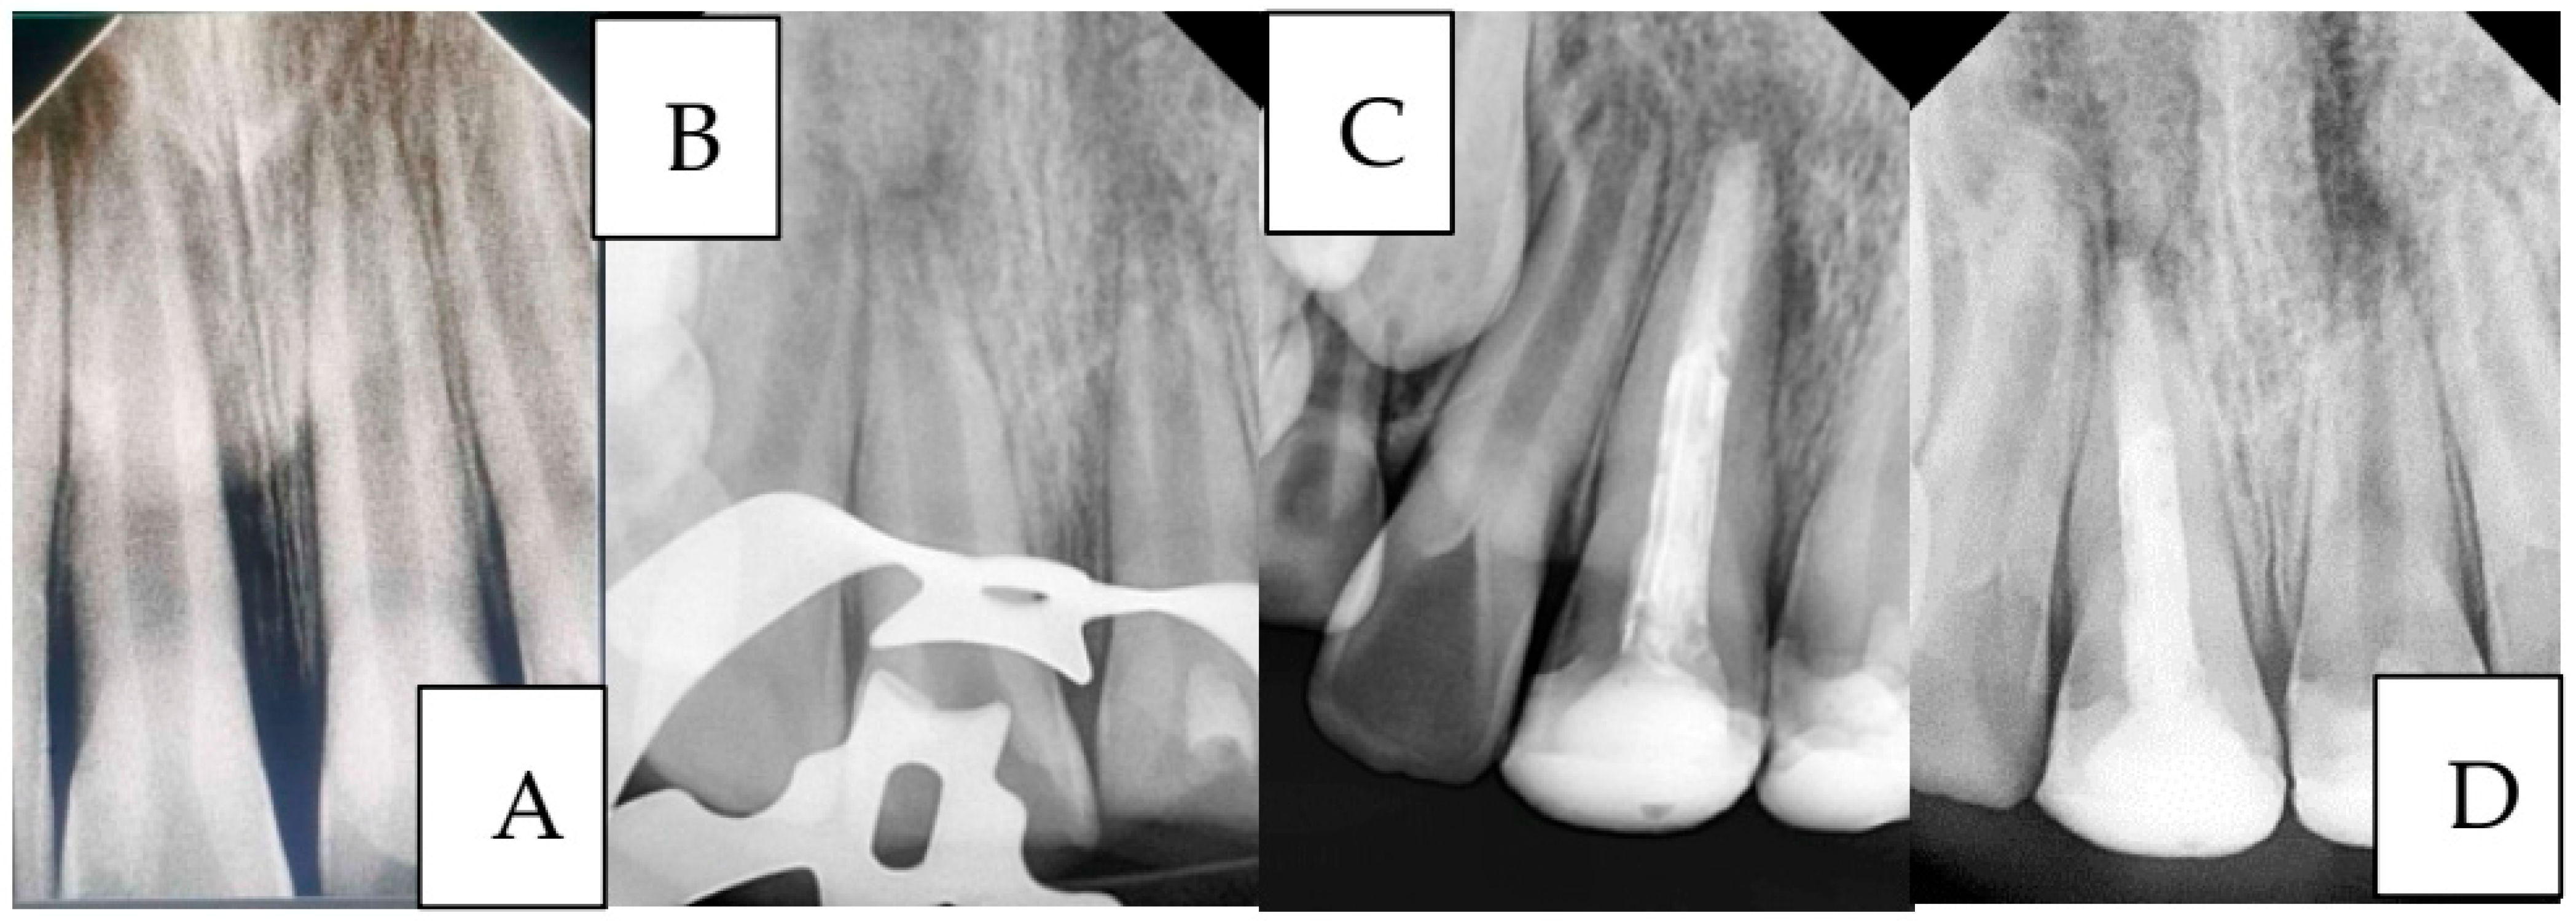

Figure 6. A case of managing anterior teeth with a history of repeated trauma: (A): Diagnostic radiograph, (B): Radiograph showing working length determination for tooth #11 and MTA pulpotomy for tooth #21 (C): Radiograph showing the placement of MTA apical plug and final restorations, and (D): Two-year follow-up radiograph showing successful treatment outcome of tooth #11 and failure of tooth #21.

Case 3 (Figure 6):

A 9-year-old child presented to the Department of Pediatric Dentistry with a history of recurrent dental trauma. The first injury, one year prior, had resulted in an uncomplicated crown fracture of tooth #11, still untreated. In contrast, the second trauma, one month earlier, caused an uncomplicated crown fracture of tooth #21. The child’s main complaint was pain associated with tooth #21. Routine radiographic examination revealed pulp necrosis in tooth #11. Vital pulp therapy with MTA was performed on tooth #21, whereas tooth #11 was managed with an MTA apical plug.

A two-year follow-up radiograph showed a marked reduction in the apical radiolucency of tooth #11 and the formation of a mineralized apical barrier adjacent to the plug. In contrast, tooth #21 later developed symptoms of acute apical periodontitis, necessitating additional endodontic intervention.